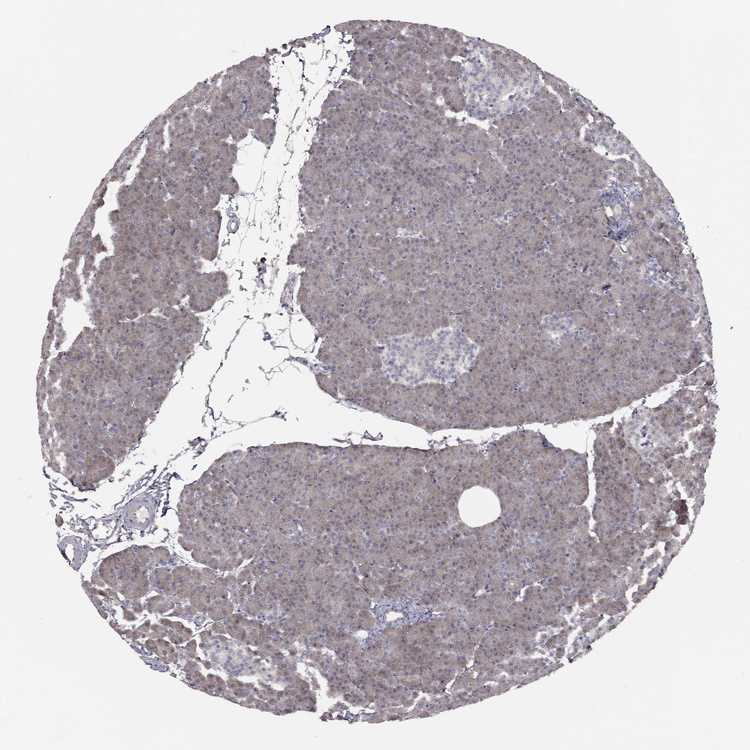

PANCREAS - Antibody stainingi

Antibody staining in the annotated cell types in the current human tissue is reported as not detected, low, medium, or high, based on conventional immunohistochemistry profiling in selected tissues. This score is based on the combination of the staining intensity and fraction of stained cells.

Each image is clickable and will lead to virtual microscopy that enables deeper exploration of all samples and also displays staining intensity scores, fraction scores and subcellular localization as well as patient and tissue information for each sample.

Antibody CAB079300

Exocrine glandular cells Medium

Pancreatic endocrine cells Not detected